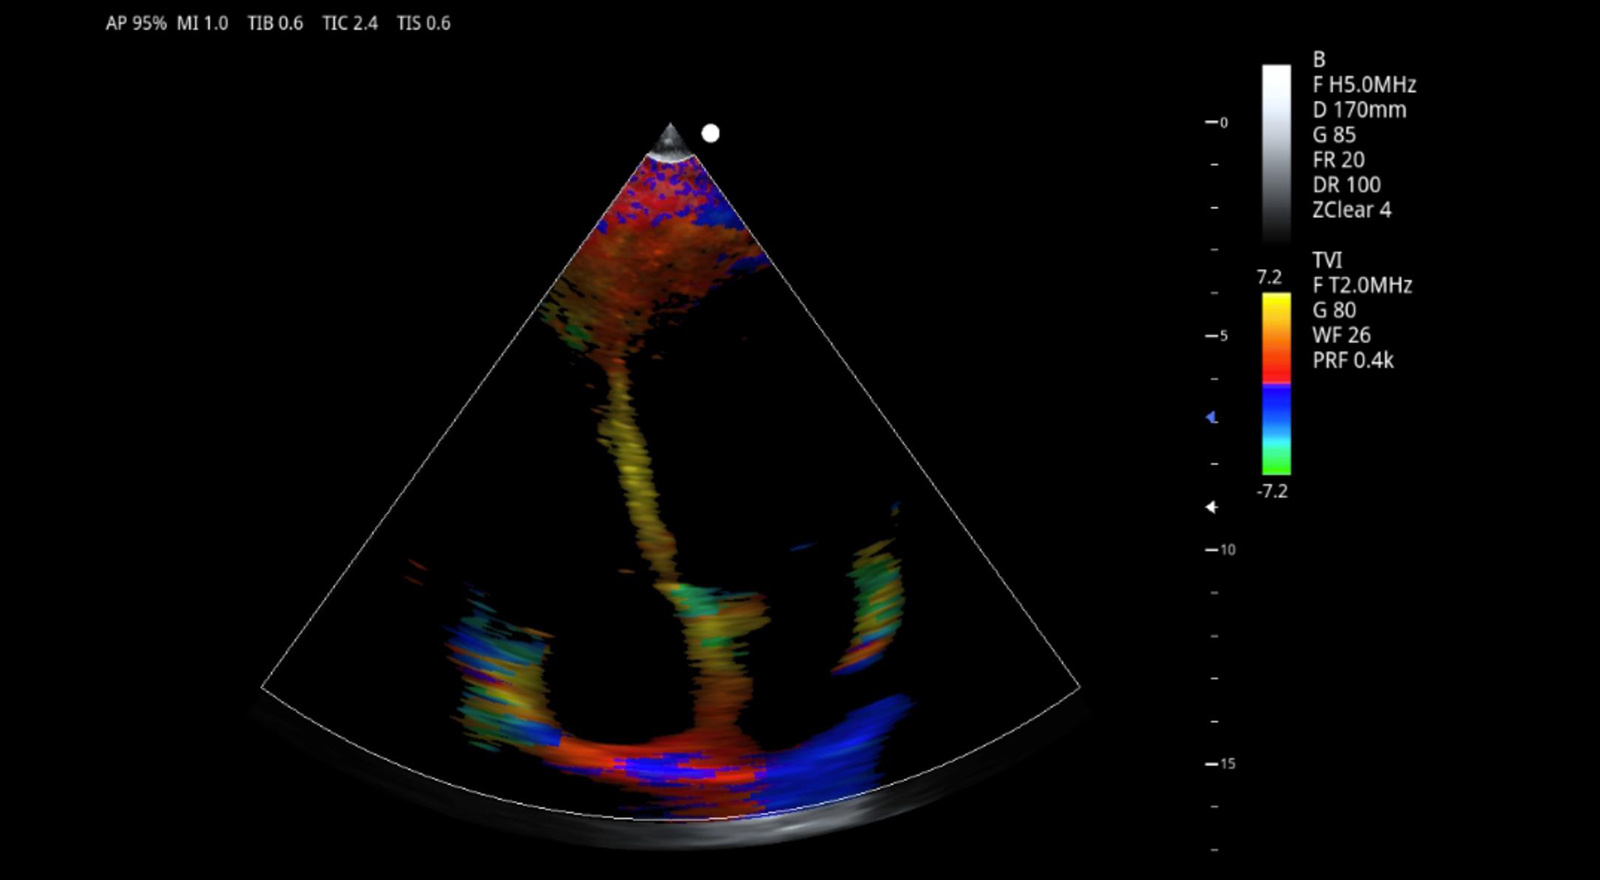

组织多普勒成像

支持TDI组织多普勒成像(TVI、TEI、TVM和TVD)